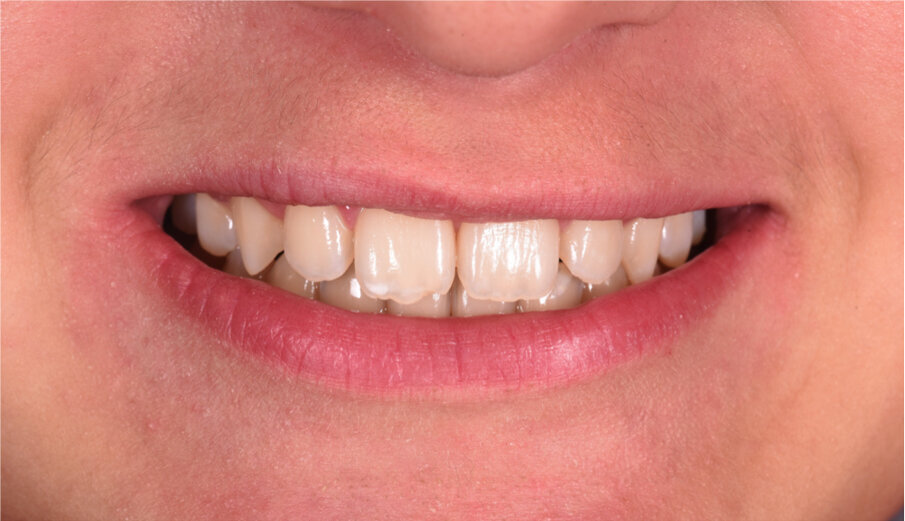

Caso 3 M.D.E Anni 2, succhiamento protratto del dito, deglutizione atipica, open bite dentale, contrazione arcata superiore. I genitori riferiscono difficoltà a respirare e raffreddori ricorrenti (Figg. 24-28).

La paziente è stata trattata con un tipo particolare di AMCOP by Micerium a forma di “ciuccio”, il quale non richiede la presa dell’impronta, ideale per i pazienti in dentizione decidua e soprattutto per i pazienti di 2-3 anni con malocclusioni evidenti. I risultati sono stati ottenuti in 6 mesi di terapia, l’apparecchio è stato portato tutte le notti ed 1 ora durante il giorno. Dopo aver ottenuto il risultato l’AMCOP by Micerium viene portato per altri 6 mesi solo la notte per garantire la stabilità e per recuperare la funzione linguale e del muscolo orbicolare delle labbra.

Questo caso dimostra come la correzione della malocclusione funzionale, frequente nei bimbi a quest’età, sia il nostro primo obiettivo terapeutico.